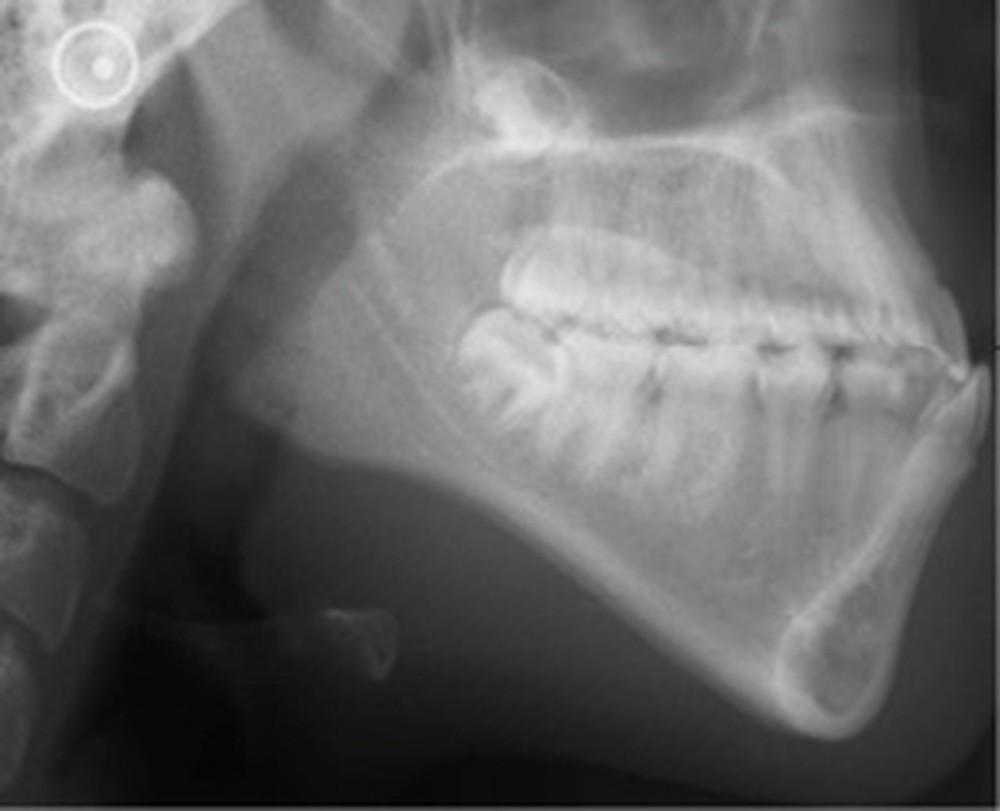

L’examen radiologique se compose d’un orthopantomogramme montrant les troisièmes molaires et des condyles symétriques, d’une téléradiographie de profil objectivant des voies aériennes supérieures libres, et d’une radiographie du poignet (stade de croissance selon Greulich et Pyle : CS6 = fin de croissance).

L’analyse céphalométrique de Tweed met en évidence les valeurs suivantes : FMA 37° (typologie hyperdivergente), SNA 89°, SNB 90°, ANB -1° et AoBo -6 mm (classe III squelettique), I/F 112° (vestibulo-version incisive maxillaire) et IMPA 84° (linguo-version incisive mandibulaire) : compensations de classe III.

L’analyse de Ricketts conclut à une classe I squelettique sur un schéma méso tendance dolichofacial avec une vestibulo-position de l’incisive mandibulaire.

Selon Sassouni, Anisa est rétro-archiale, en classe III squelettique de 9 mm et alvéolaire de 12 mm avec une incisive maxillaire en vestibulo-position de 6 mm.